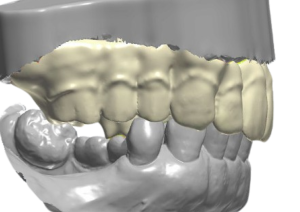

- 資料搜集:術前一週,郭光哲醫師會為患者進行 3D 數位口腔掃描及拍攝口內外照片。根據醫師所制定的治療計畫,醫師和技師將共同討論並依照患者的五官特徵,客製化手術當天所需的臨時假牙

- 植牙手術:手術日早上,郭光哲醫師會依照治療計畫在每顎植入植體,植牙過程在舒眠麻醉下執行,並由專業的麻醉科醫師協助監控,讓患者一覺起來輕鬆完成手術,毫無壓力。為了追求完美,郭光哲醫師在每個 All on X 手術中都會搭配最新 Navident 4 (AR擴增實境數位導航),完美執行精準與安全。手術完成後,需要等待2到6個月,讓植體與骨頭完全密合。接著郭光哲醫師會開始製作正式假牙讓患者試戴,並根據病人的反饋進行調整,最後製作出兼具美觀與功能的正式假牙。

- 假牙印模:手術完成後,需要等待3到6個月(瑞士 Straumann植體因有特殊表面處理,加速骨整合只需三個月),讓植體與骨頭完全密合。而後郭光哲醫師會開始製作正式假牙讓病患試戴,並根據病人的反饋進行調整。最後製作出兼具美觀與功能的正式假牙。